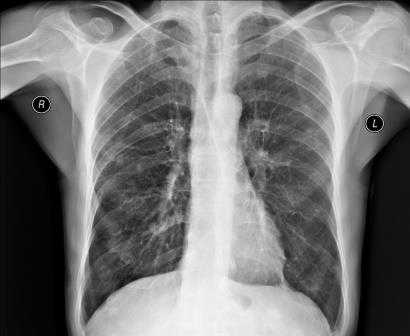

Рентгенография грудной клетки - это метод диагностики, позволяющий получить изображение органов грудной полости с помощью облучения рентгеновыми лучами. Различные ткани организма в зависимости от своей плотности по-разному пропускают рентгеновы лучи, а значит, по-разному отображаются на снимке (рентгенограмме).

Рентген грудной клетки дает возможность изучить костные структуры (ребра, грудину, позвоночник), легкие, плевру, бронхи и трахею, сердце и средостение, а также оценить состояние мягких тканей этой области.

Для выявления патологических изменений сердца и оценки их влияния на сосудистое русло легких наиболее часто применяют рентгенографическое исследование грудной клетки, позволяющее получить изображение средостения, сердца и легких.

Снимки обычно делаются в заднепередней и левой боковой проекциях. В заднепередней проекции благодаря уменьшению расстояния между сердцем и рентгеновской пленкой изображение сердца получается более четким и менее искаженным, чем в переднезадней. У лежачего пациента можно воспользоваться передвижным рентгеновским аппаратом, но он позволяет делать снимки только в переднезадней проекции.

Нормальная картина

В норме на снимках, выполненных в заднепередней проекции, ширина грудной клетки по меньшей мере в 2 раза превышает поперечный размер сердца. В то же время в переднезадней проекции относительные размеры и положение сердца могут быть другими; возможно усиление тени сердца и дуги аорты. Когда исследование проводится с контрольной целью, рентгенограммы грудной клетки должны подтверждать правильное положение катетеров и водителей ритма.

Изменение формы сердца обычно заключается в увеличении левого или правого желудочка, левого предсердия или даже нескольких полостей. При увеличении левого желудочка в заднепередней проекции левая граница сердца становится круглой и выпуклой с боковым расширением в своей нижней части, а в боковой проекции определяется выбухание левого желудочка кзади. При увеличении правого желудочка в заднепередней проекции наблюдается вторичное изменение левой границы сердца за счет расширения тени легочной артерии, а в боковой - расширение тени выносящего тракта правого желудочка. При увеличении левого предсердия его плотность на рентгенограмме в заднепередней проекции увеличивается вдвое, левая граница сердца сглаживается, левый главный бронх смещается кверху. В редких случаях правая граница сердца над проекцией правого желудочка расширяется кнаружи. В боковой проекции определяется выбухание левого предсердия кзади. Начальными признаками застоя в малом круге кровообращения на снимках, сделанных в заднепередней проекции, являются расширение тени легочных вен в верхнебоковой части корней легких и сосудистые тени, расположенные горизонтально вдоль нижней части правой границы сердца. Хроническая легочная венозная гипертензия приводит к формированию рисунка по типу оленьих рогов (из расширенных верхних и нормальных или суженных нижних легочных вен). При остром отеке легких увеличение плотности в центре легочных полей может по форме напоминать бабочку. Интерстициальный отек легких может напоминать снежные хлопья на фоне легочных полей.